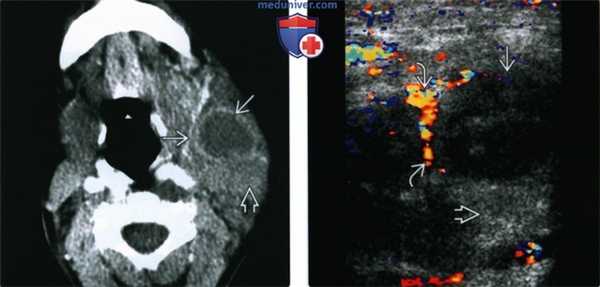

(Слева) КТ с КУ, аксиальная проекция, поднижнечелюстное образование пониженной плотности, имеющее четкие контуры и тонкое периферическое кольцо накопления контраста №. На фоне гнойного процесса отмечается выраженное воспаление мягких тканей левой половины шеи и грудино-ключично-сосцевидной мышцы, а также реактивное воспаление лимфоузлов.

(Справа) УЗИ, продольная проекция, лимфоузел уровня IB. Гипоэхогенное округлое образование с дистальным акустическим усилением, характерным для кистозных образований. При допплеровском сканировании была выявлена повышенная васкуляризация по периферии образования.

4. УЗИ при нагноении лимфатических узлов:

• Пониженная эхогенность в центре с дистальным акустическим усилением

• Повышенная васкуляризация по периферии при допплерографии:

о Очень низкие значения акустического сопротивления и пульсационного индекса